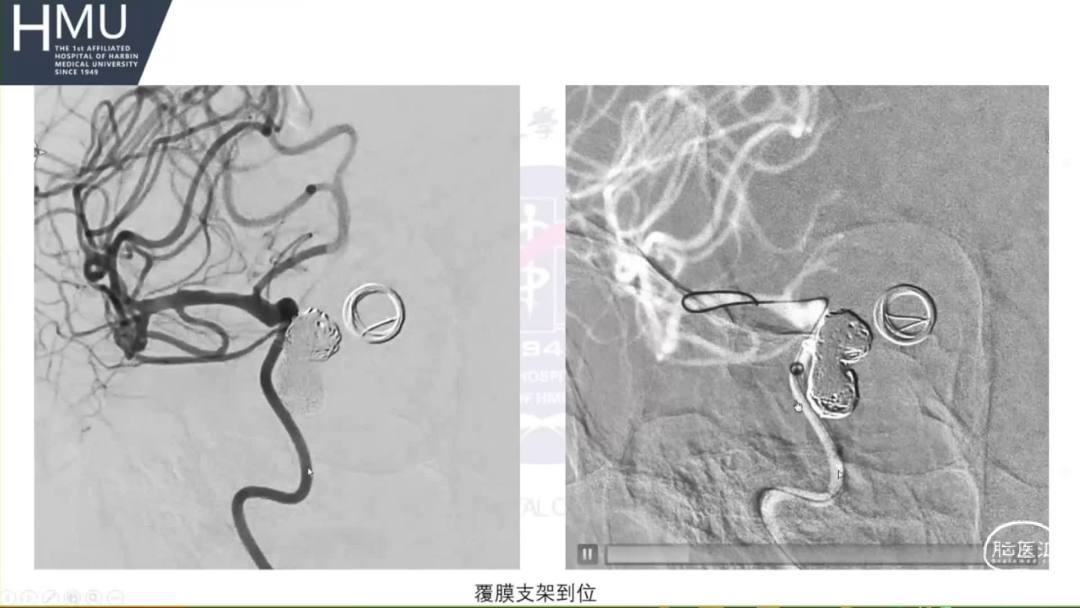

21:00覆膜支架置入术